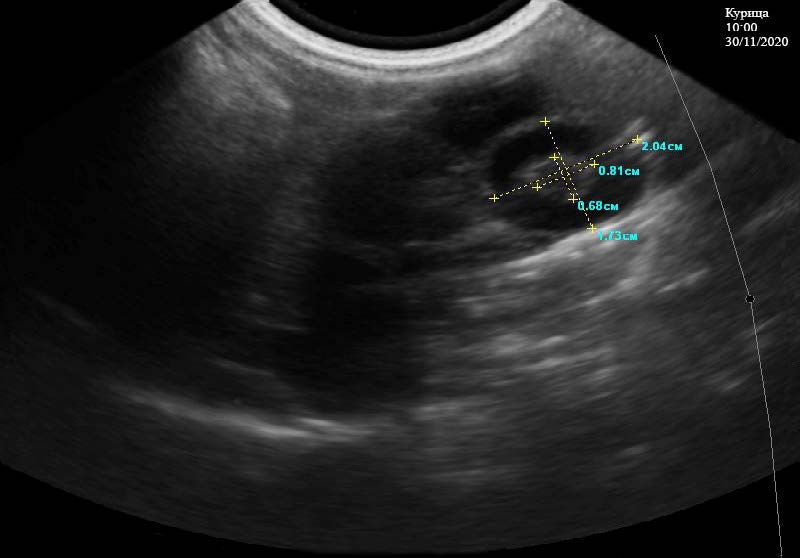

Второй этап исследования осуществляли в 10:00 30.11.2020 г. Отмечается желток, покрытый вителлиновой оболочкой, который расположен в центральной части белкового отдела яйцевода имеет размеры 0,81*0,68 см, большую плотность и хорошую эхогенность. На его периферии расположено небольшое количество белка 1,73*2,04 см с более низкой плотностью. При этом, на снимке отмечается хорошо контурированный черный диск (рис. 3).

Рис. 3. Краниальная часть белкового отдела у курицы кросс «Хайсекс белый», с наличием желтка с оболочками. 10:00 ч. 30.11.2020 г.